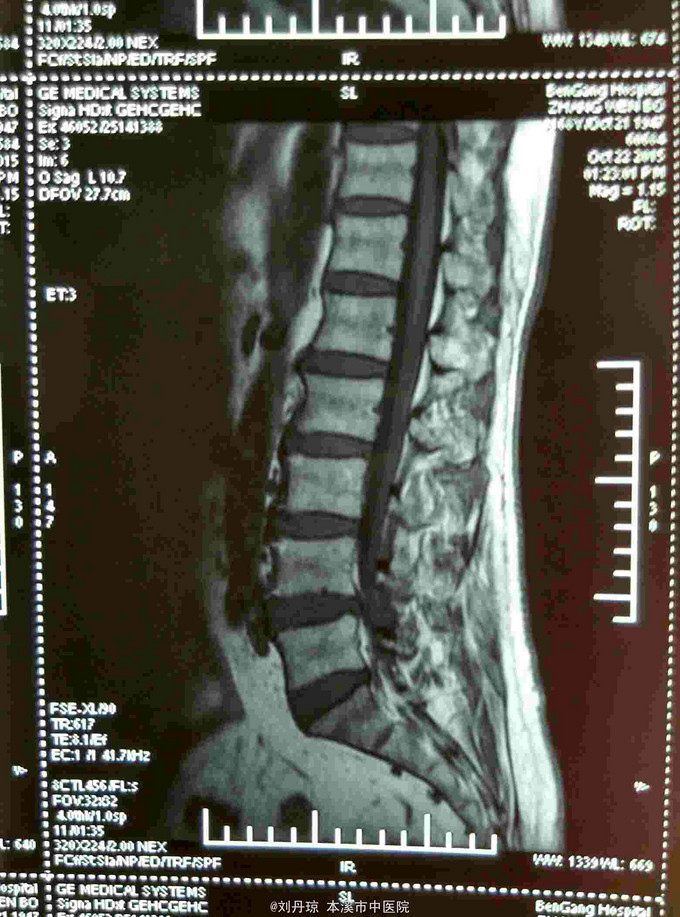

腰部间歇性钝痛伴左下肢放射痛麻木感半年。患者半年前无明显诱因感腰部间歇性钝痛伴左下肢放射痛麻木感,经多家医院治疗未见明显好转,今日来我院门诊求治,门诊医师以“ 腰椎间盘突出症、骶管囊肿 ”收入院治疗。

L4-S1棘突左侧1厘米压痛阳性,直腿抬高试验左40º右60º,加强试验左侧(阳性)右侧(阴性),腰椎功能障碍。左腿前外侧及足背外侧感觉减弱。 辅查CT: 腰椎间盘突出症、骶管囊肿